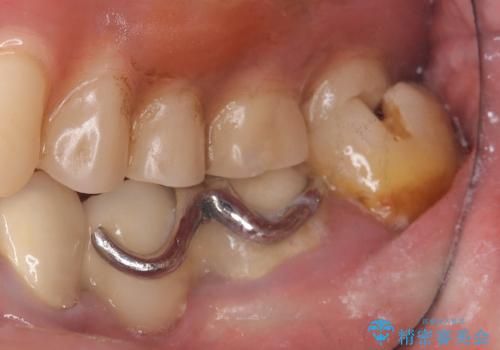

メタルインレー脱離後の窩洞をセラミックインレー窩洞に再形成し直し印象しています。遠心・舌側面のカリエスの除去、残存歯質の破折リスクを考えアンレー形態となりました。

アンレー装着時にはラバーダム防湿を行っています。